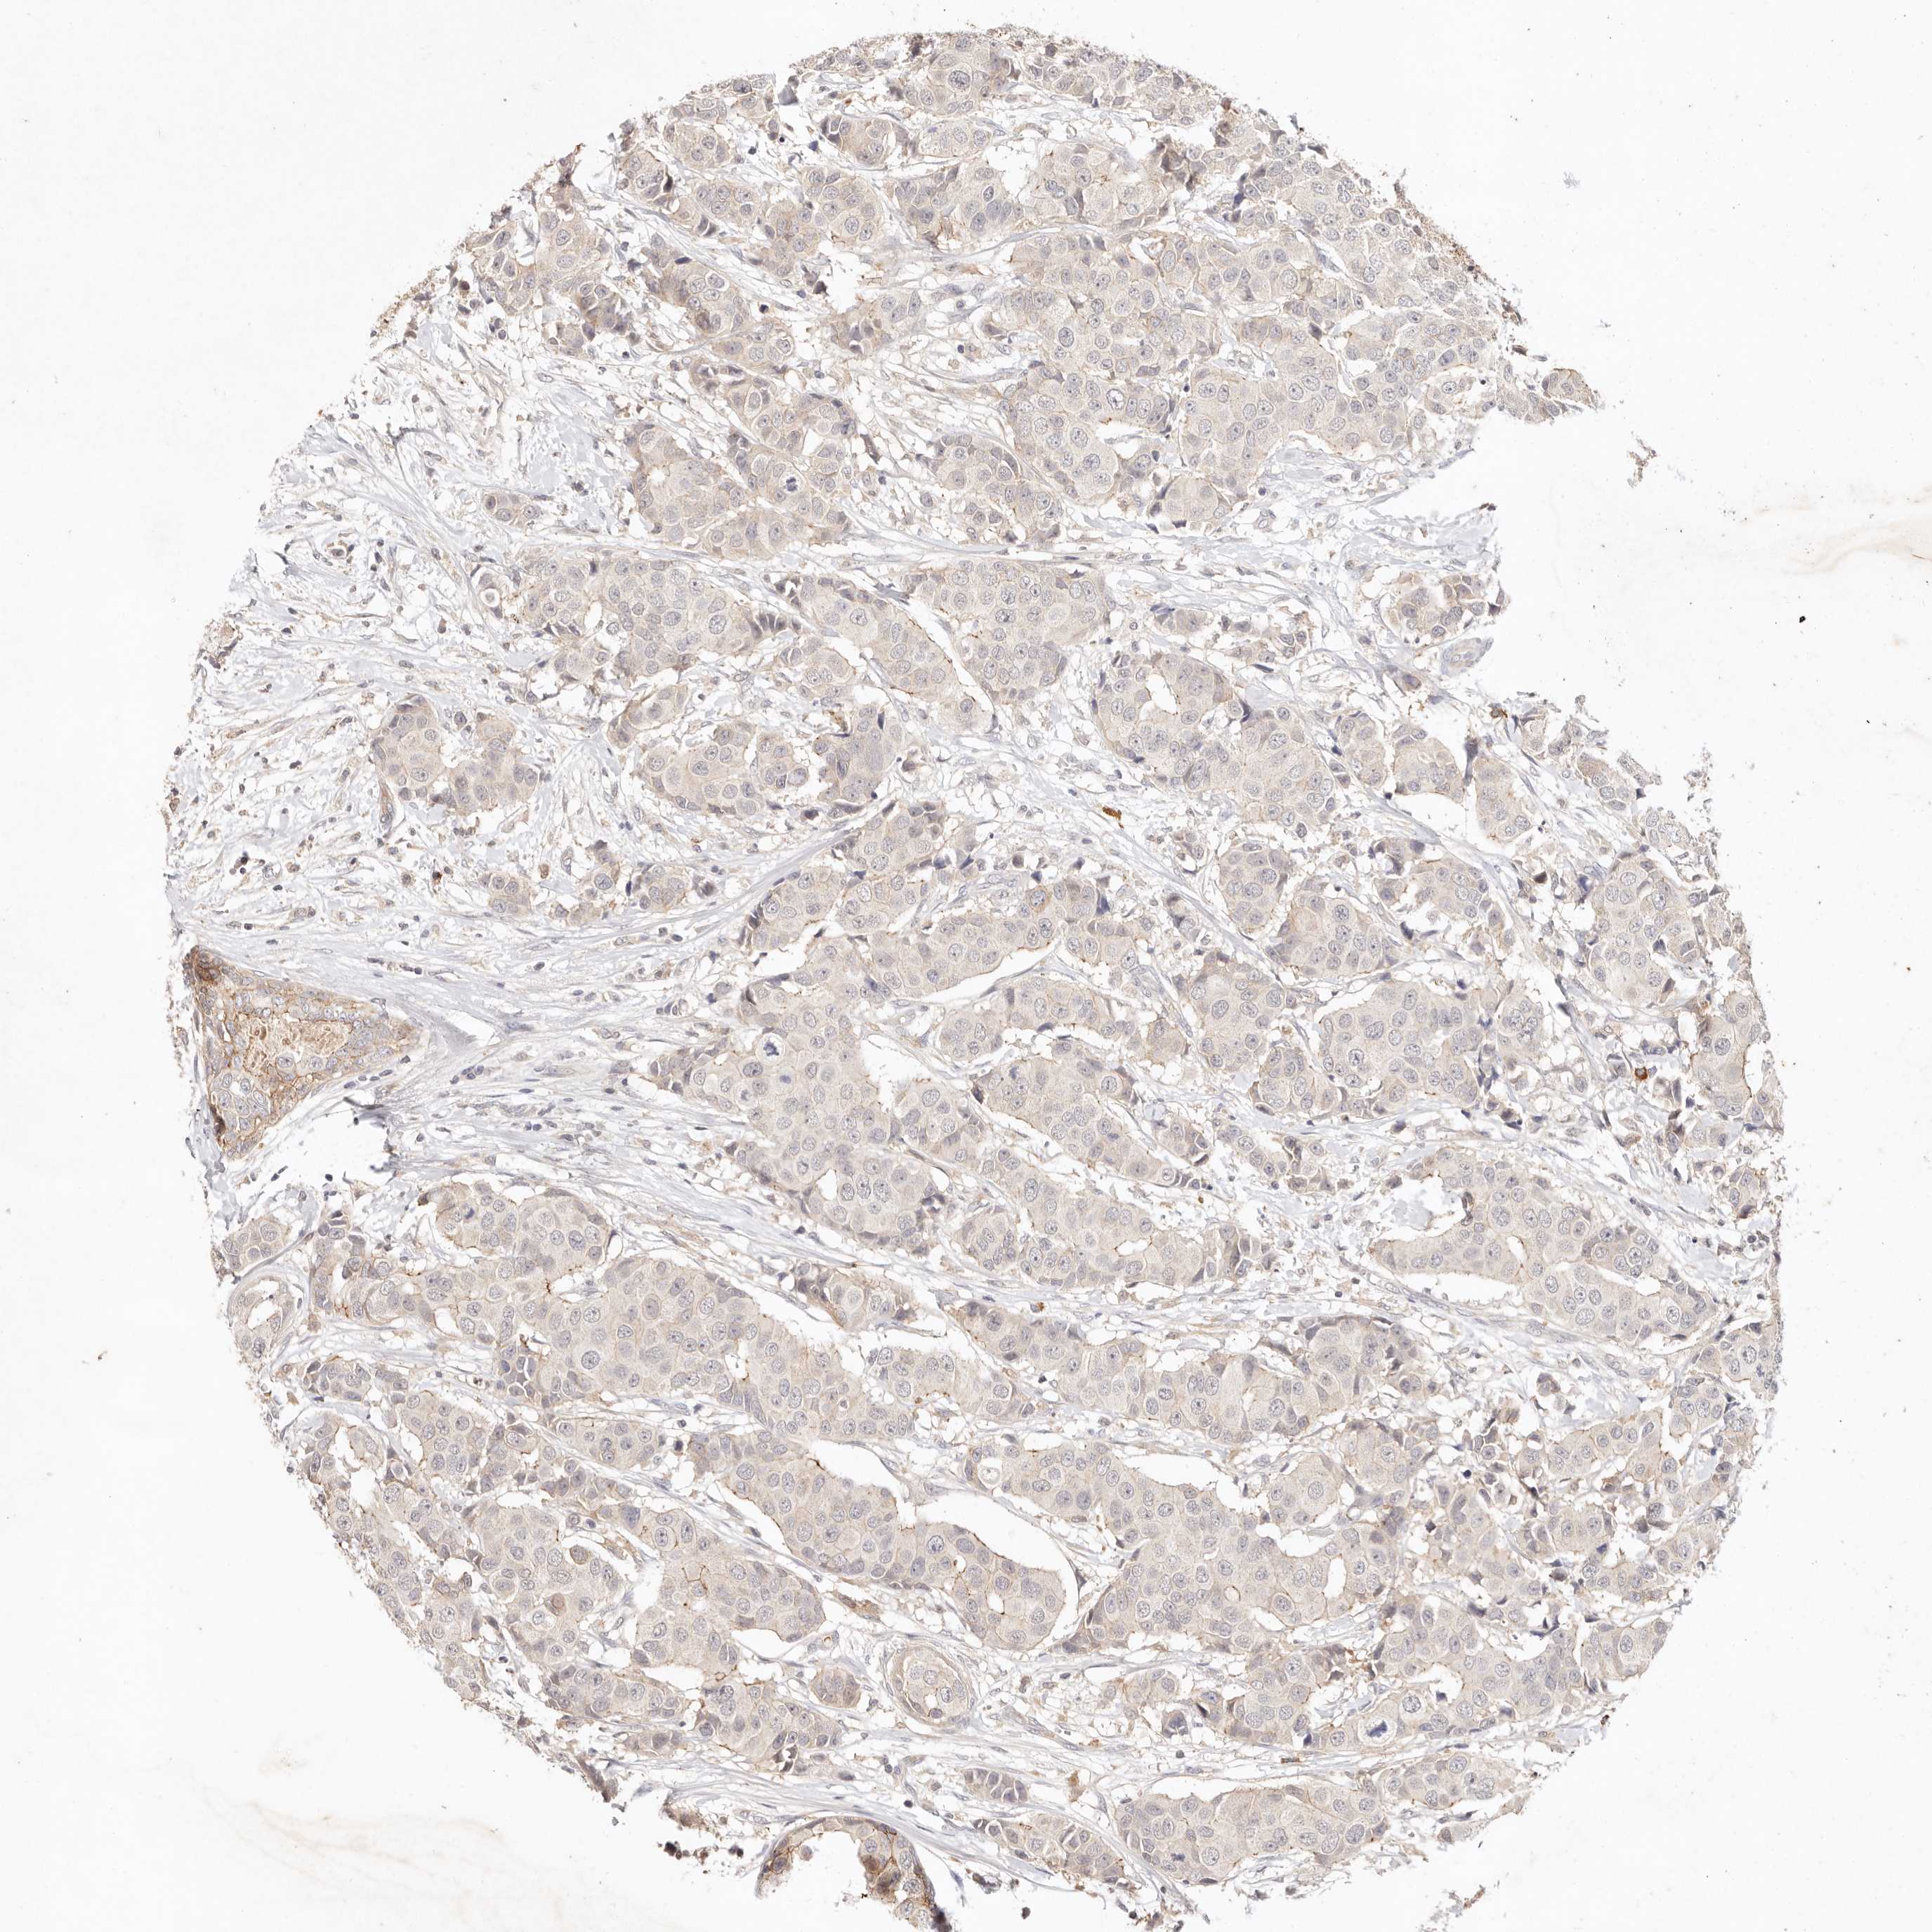

BRCA TCGA BRCA VALIDATION PROTEIN EXPRESSION